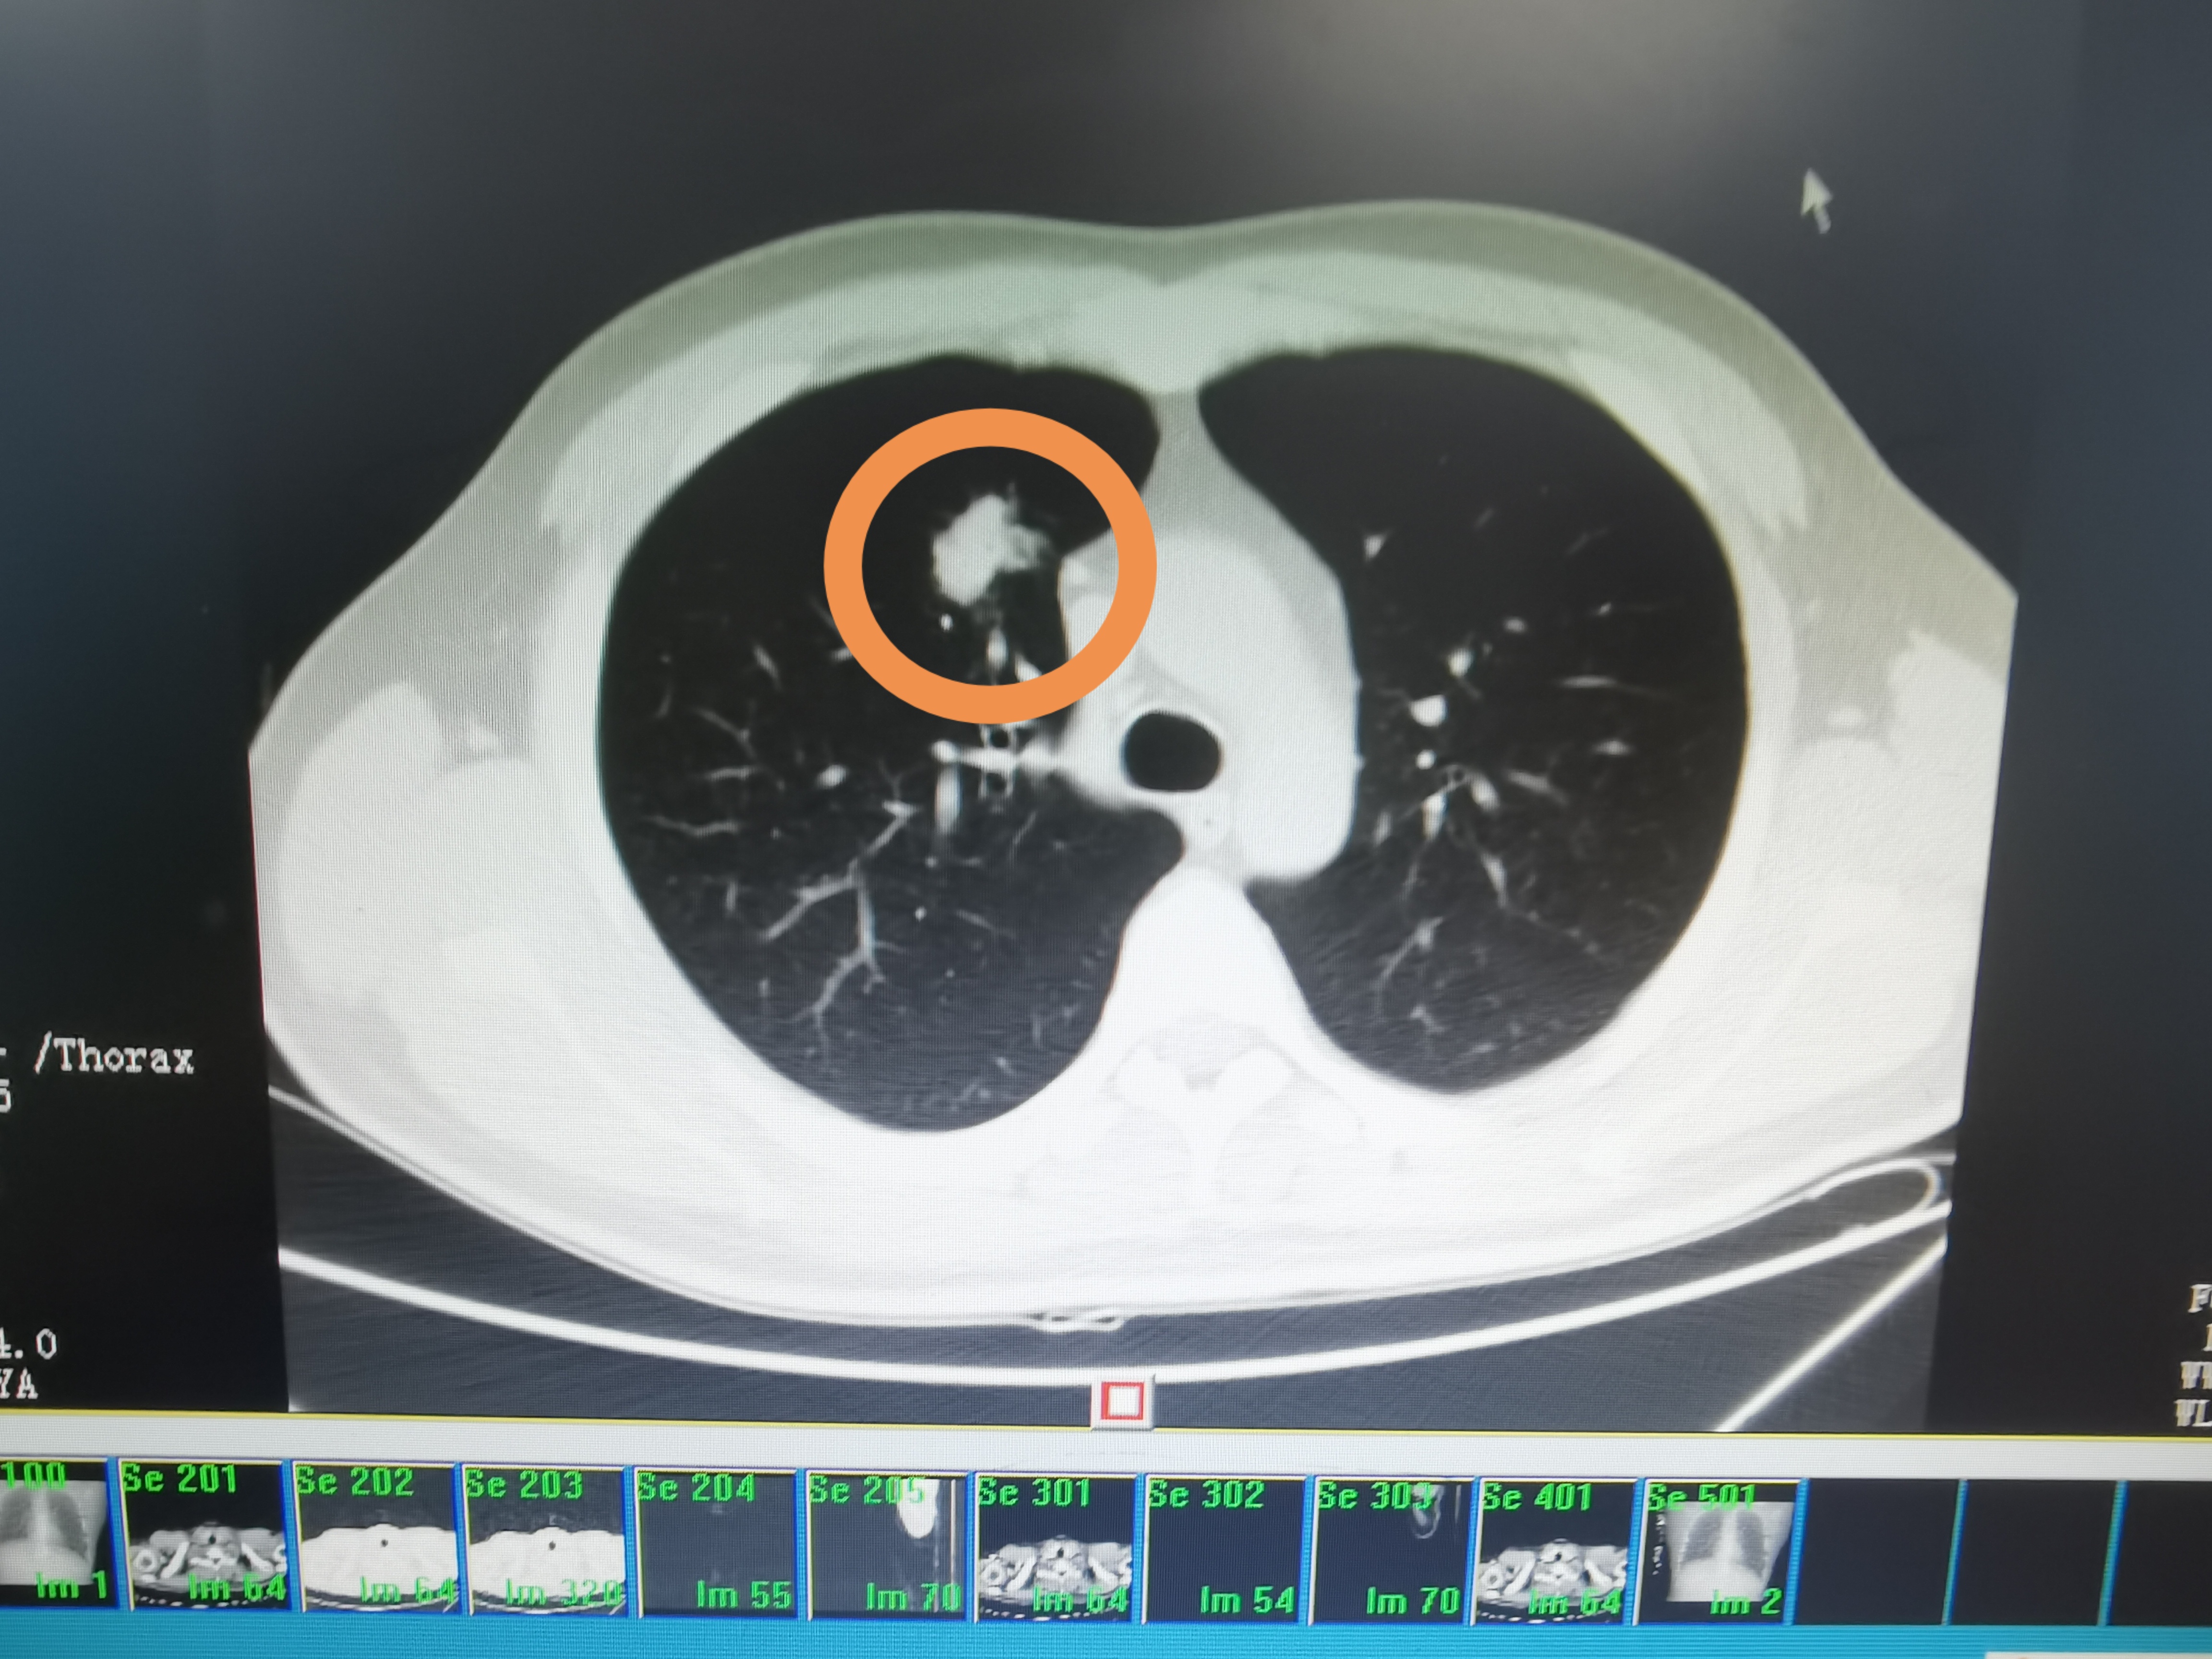

王医生(化名)是省内某市级医院的一名呼吸内科医生,前不久拿到肺部复查的CT结果,半年前体检发现的右肺小结节居然长大了,此时王医生和许多肺结节患者的心情一样,惴惴不安,因为作为一名呼吸科医生,肺部小结节长大预示着什么,心里已经有了好几种可能的答案。他知道只有明确的诊断才能尽早针对治疗。这时候,他想到了捷克论坛 蒋永亮主任,他曾多次听说过蒋永亮主任及其团队的经皮肺穿刺活检术精准快速,于是找到了蒋永亮主任。

来到捷克论坛 呼吸内科见到蒋永亮主任后,蒋主任第一时间组织经皮介入团队对王医生的肺部影像进行仔细分析,制定穿刺活检路线过程中,王医生自己也加入到讨论当中,他觉得这次不仅是以患者的身份接受治疗,还是以一名呼吸科医生参与学习。科室在王医生入院的第二天便安排进行穿刺活检,从入院到最终确诊,蒋主任及其团队通过精准定位,运用精湛的穿刺技术,一针到位取到病灶组织,病理确诊为结核,仅仅只用了4天,消除了王医生半年来的顾虑。术后王医生感慨道:“真是一次令人难忘的经历。”